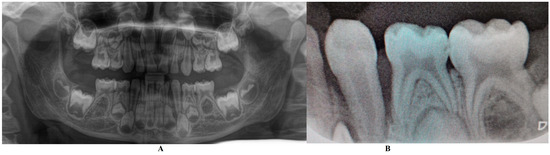

Figure 4.

Tooth loss (September): (A)—alveolar socket with no inflammation signs, (B,C)—tooth with root apical third resorptive signs and traces of calculus and dental plaque in the root cervical area and middle third (the potential origin of the periodontal problems).

Eventually, as expected, the tooth was lost at the beginning of September, and alveola healed without further problems (Figure 4).

The bacterium types present in this case (i.e., Fusobacterium nucleatum/periodonticum and Capnocytophaga spp.) were reported not to produce ATP molecules [13]; nevertheless, the presence of Fusobacterium nucleatum has been reported to be associated with a high number of late colonizers associated with periodontal destruction [12,13], which might explain some of the localized aggressive periodontal destruction. Nevertheless, on the lost tooth (Figure 4B,C), some traces of calculus and plaque are visible, confirming the source of periodontal bacteria.

Retrospectively speaking, the tooth showed visible traces of plaque and calculus deposits (Figure 4B,C), which could be present on the tooth throughout the infectious episode, going unnoticed, and representing the original source of bacteria. Nevertheless, it must be emphasized that full professional scaling and root planning was extremely difficult in this case, due to the child’s small age and problems of collaboration (hence the importance of individualizing periodontal treatment).